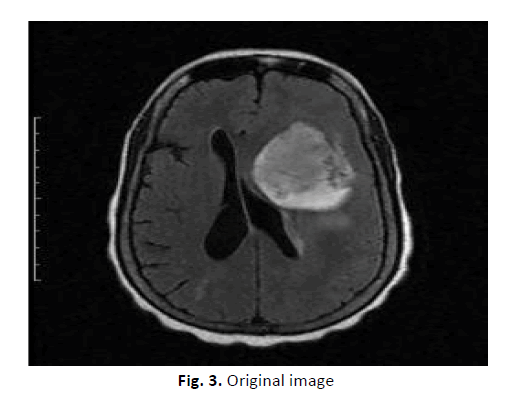

This experimental study was conducted to find an accurate brain tumour segmentation method using a parallel computing algorithm. For ten patients with T1 and T2 MRI data, a new potential field segmentation algorithm was used. In total, 200 MRI images were used in this was study. The manually defined fields compared segmented GTVs with the Q, DSC, and other measures. Figure 3 shows the original images before applying watershed segmentation. Figure 4 shows the application of the Sobel edge masks that were used for gradient magnitude computation. Masks, image filters, and a few simple arithmetic methods were used to measure the gradient magnitude. The gradient is high at the object's border, and those of the objects are (mostly) low inside. Figure 5 shows the results of the opening-by-reconstruction algorithm using the opening-close reconstruction filter.

Figure 3: Original image